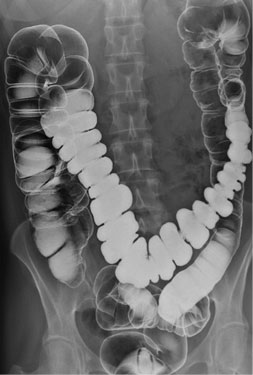

Normalement la colon est un tube cylindrique a

paroi lisse comporte en cinq partie . Le colon droit depuis

le caecum debute le ceocum jusqu'a l'angle droit , le colon

transverse , le colon gauche , le sigmoide et le rectum

Le colon est

en aspect segmentation haustrale a bien

visible de droite a gauche . Epaisseur des

haustrations ne depassent pas de 2 a

3mm . Calibre du colon etre inferieure de 5

a 6cm

Image une

lavement baryte mono de contrast . La region ileo -

ceacal est si nette . Une partie de ileon peut

voyait . Appendice se presente dans cette cas |

Lavement baryte ( mono

contrast ) : Image radiologique normale du colon :

Caecum , colon ascendant , angle droit , colon

trasverse , colon gauche , colon sigmoide et rectum

. |